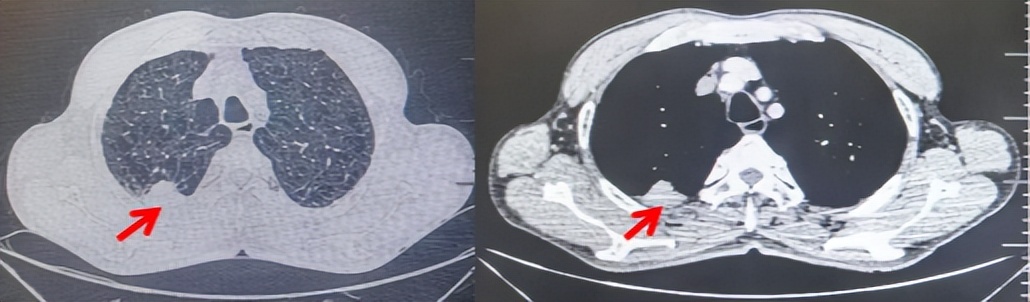

71岁男性,高血压病史20年,口服药物治疗,无糖尿病、心脏病等基础疾病,吸烟史50年,20支/天,已戒1年余,无饮酒史,无肿瘤家族史。2023.11因咳嗽、咳痰行胸CT检查:左肺下叶占位性病变,大小约12mmx8mm(如图5)。2023.11.20行“单孔胸腔镜左肺中下叶切除、肺门及纵隔淋巴结清扫、胸膜粘连松解术”;术后病理:(左肺下叶)结合免疫组化鳞状细胞癌(中、低分化),局部见脉管内癌栓,未见确切神经侵犯,(气管切缘)净。(淋巴结)未见转移癌0/19(4组0/1;5组0/1;6组0/2;7组0/1;9组0/1;10组0/2;11组0/3;12组0/2;13组0/2;14组0/4)。术后分期pT1bN0M0 IA期,术后定期复查。

图5:患者手术前(2023.11)胸部CT肺窗及纵隔窗

图6:患者胸膜及纵隔转移(2024.09)胸部CT肺窗及纵隔窗